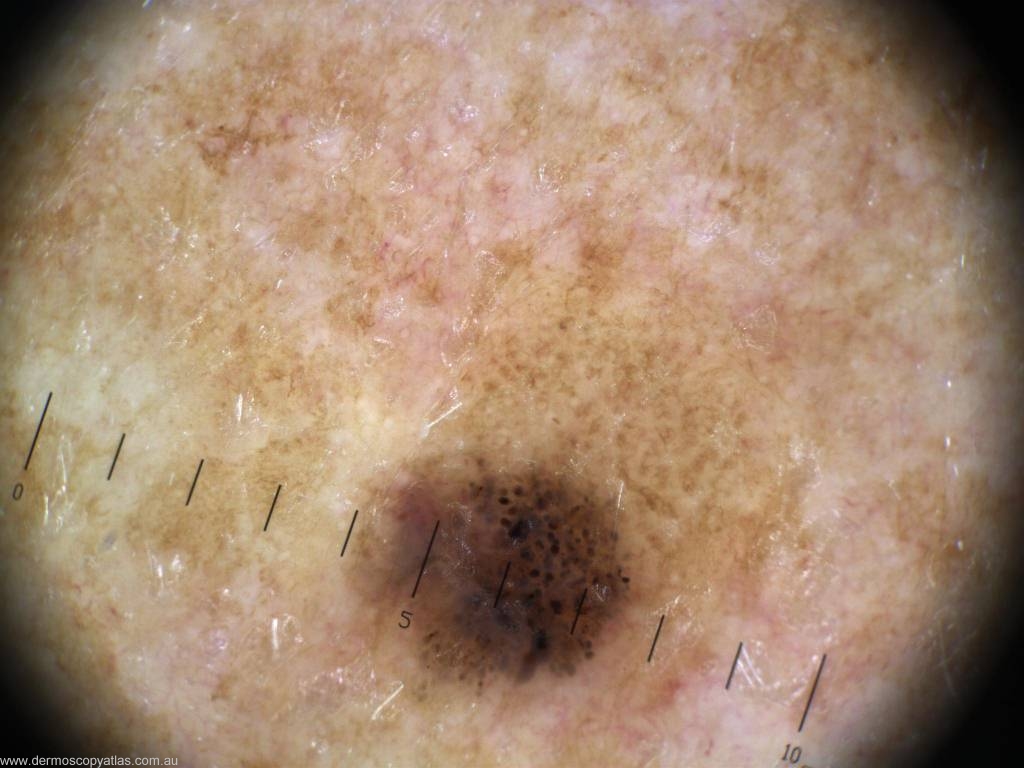

Case 11 Female aged 53. Routine check. No patient history. L arm.

Question: What is your diagnosis? Consider Melanoma in situ, Seborrhoeic keratosis, Invasive melanoma,Benign compound nevus, Dysplastic nevus, Pigmented BCC and Spitz nevus.